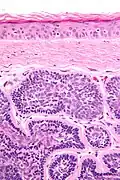

Micrograph of dermal cylindroma in H&E stain. -

Dermal cylindromas are:

- Dermal lesions consisting of nests of cells that are surrounded by hyaline (i.e., glassy, eosinophilic, acellular) material and have:

- Hyperchromatic nuclei that may palisade (columnar nuclei arranged around the periphery of the cell nests with their short axis tangential to the nest periphery), and

- Cells with lighter staining ovoid nuclei at their centre.

They lack of a significant number of lymphocytes; this differentiates them from spiradenomas.